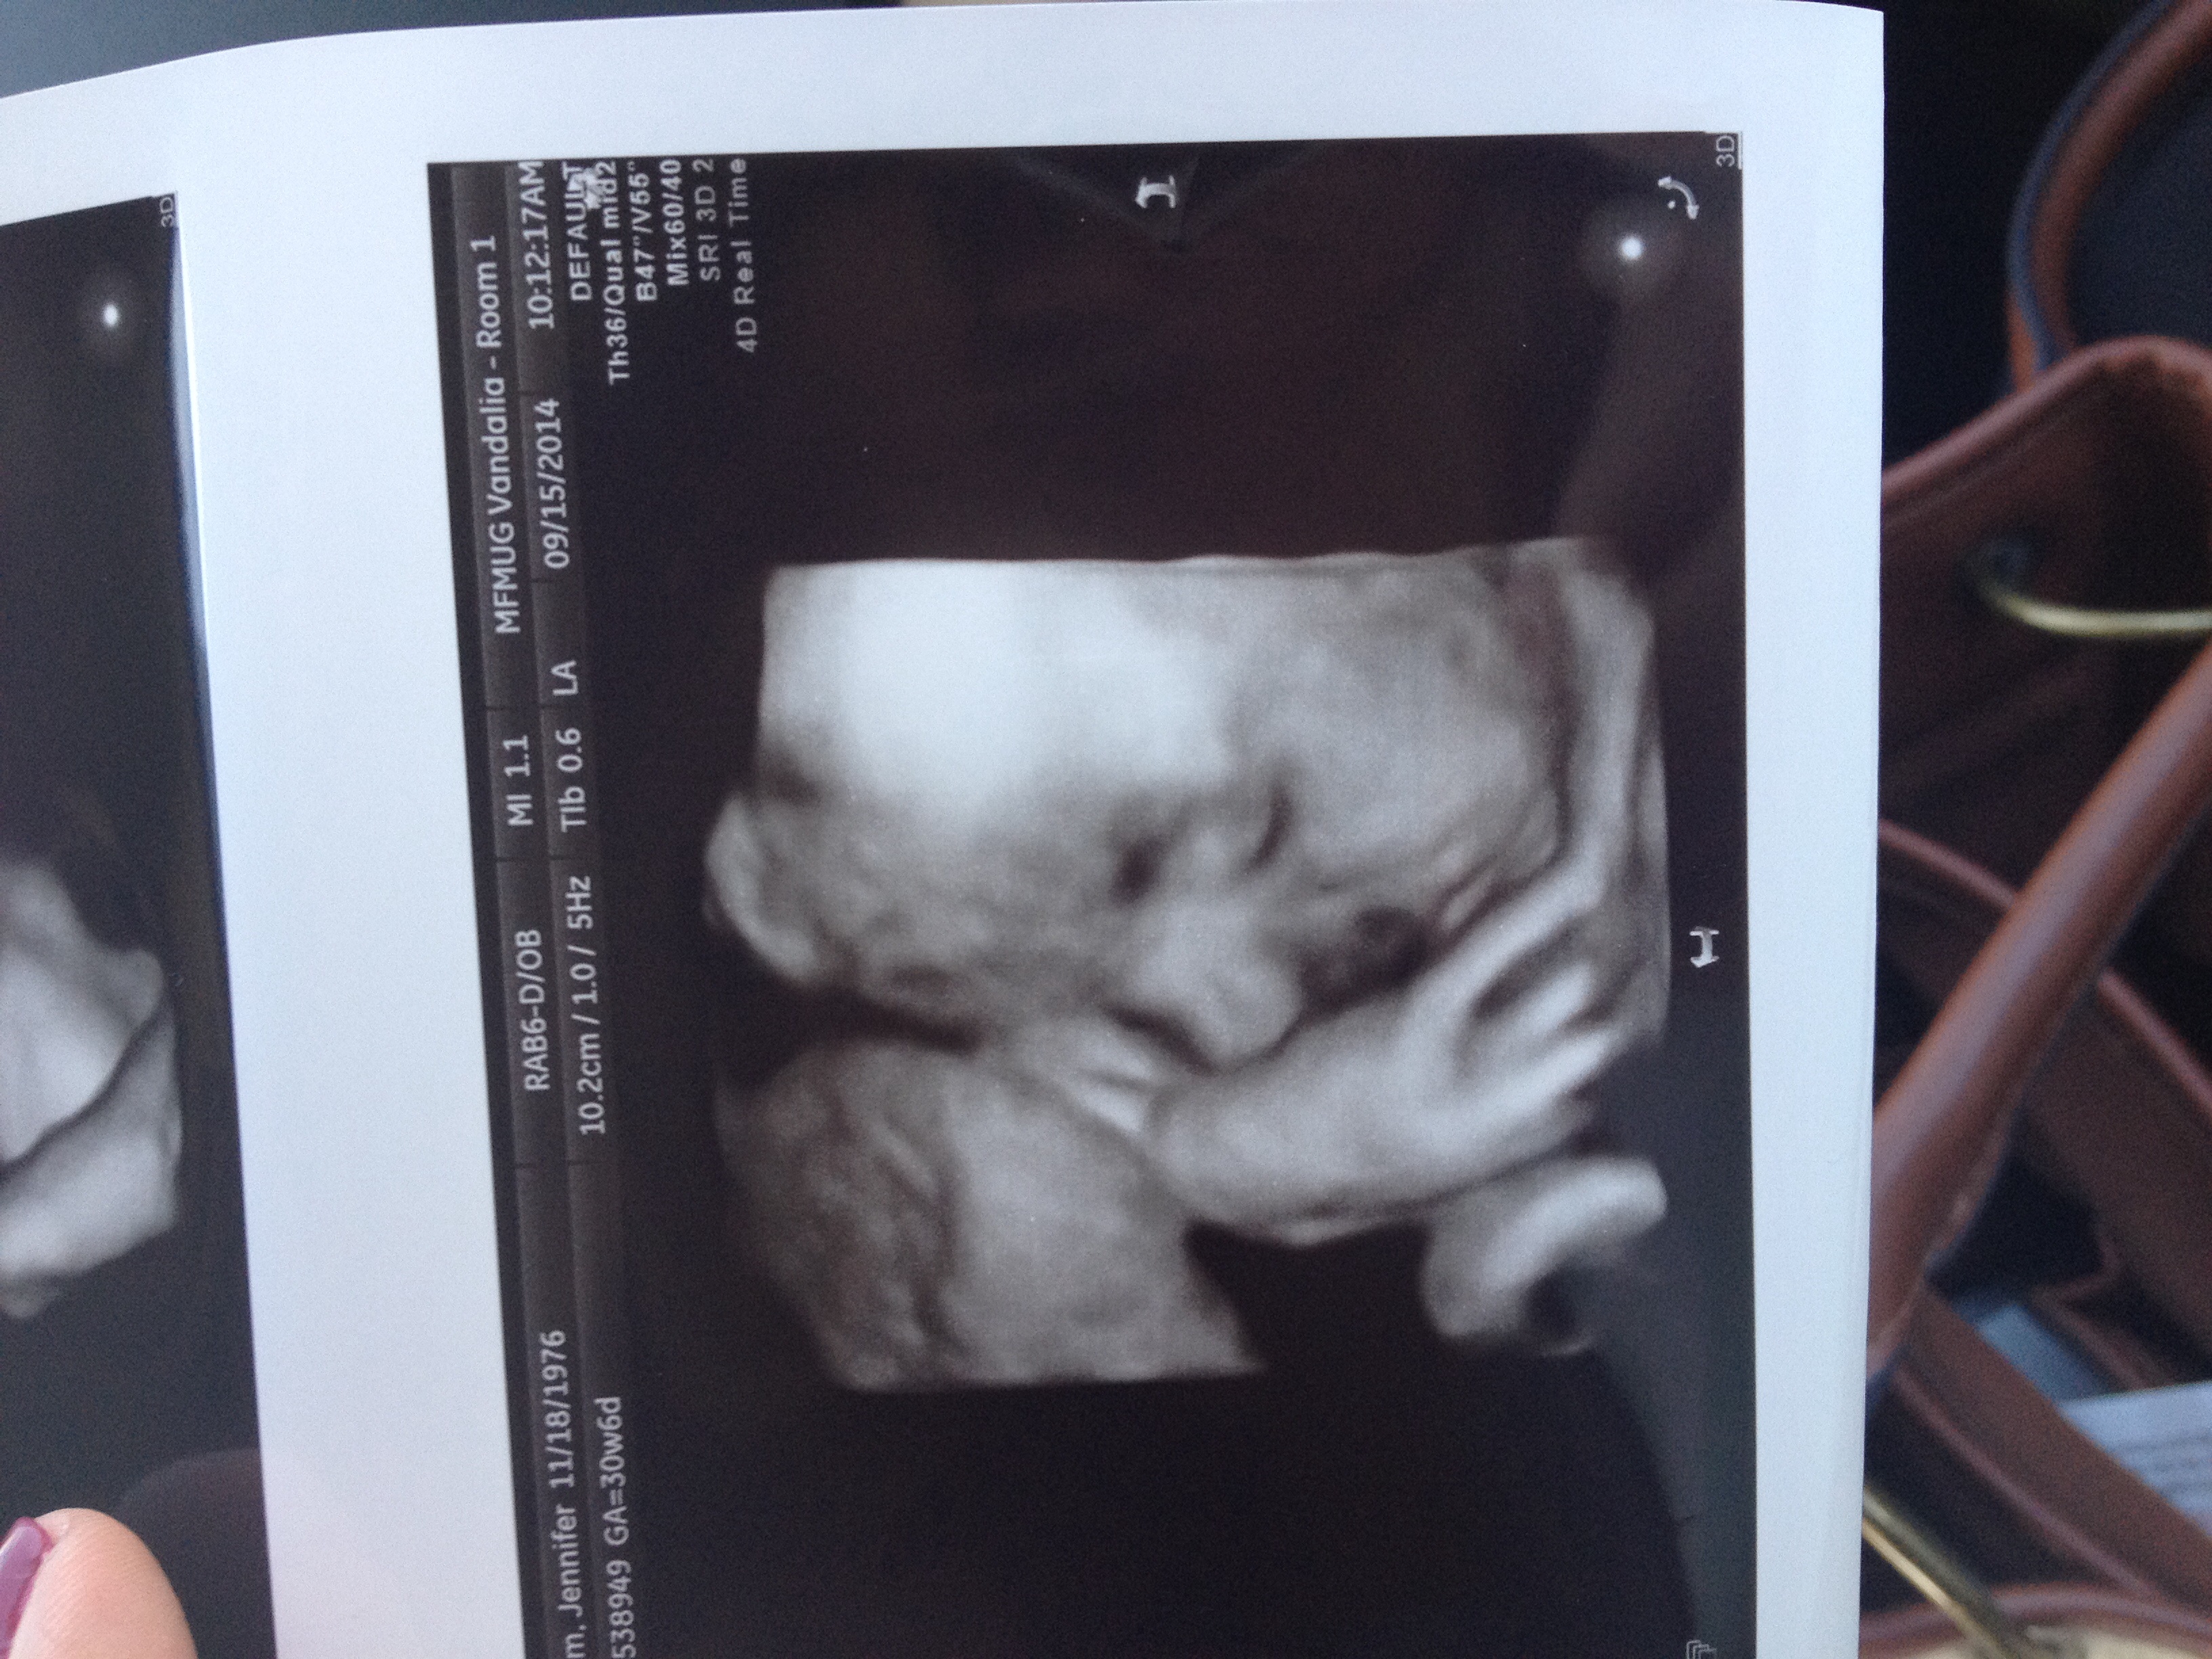

We had our 3D ultrasound today. She weighs 4.5 pounds at 30 weeks and I'm measuring a week ahead. I think I should brace myself for a big baby

Edited because it posted before I was finished